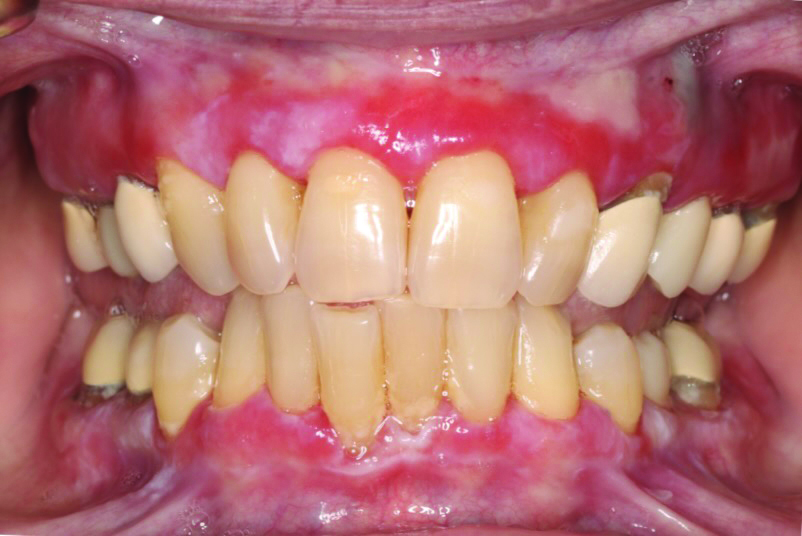

Erythematous/erosive/atrophic: Painful, red, raw mucosa, often on the gingiva (desquamative gingivitis), coexisting with reticulated areas (Figure 1).

Fig 1. Erosive lichen planus in a 47-year-old African American female patient. Erythematous, ulcerated lesions could be visualized at the gingival margin in both the maxilla and mandible. The patient reported significant discomfort associated with these lesions and aversions to acidic and hot foods due to pain after consumption.